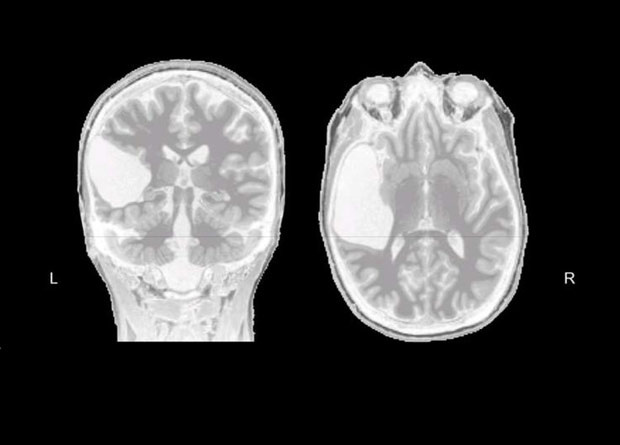

Для развития речевого центра в лобной доле (центра Брока) необходим функционирующий речевой центр в височной доле (центр Вернике) того же полушария. К такому выводу пришли американские ученые, когда проанализировали мозг женщины, у которой височная доля отсутствовала с рождения. Речевые функции у нее взяли на себя лобно-височные области правого полушария, а центр речи лобной доли левого полушария не работал. Исследование опубликовали на сайте препринтов bioRxiv.

У человека речевые функции связаны с активностью лобно-височных отделов мозга. При этом доминирующая роль в этом процессе у левого полушария. В нем наблюдается большая активность во время разговора по результатам функциональной магнитно-резонансной томографии, а при повреждении лобно-височных отделов левого полушария мозга во взрослом возрасте повреждаются речевые функции. При этом если повреждение произошло в раннем детстве, то правое полушарие может взять на себя контроль за речевыми функциями. Мы уже писали о детях, которые еще до рождения перенесли ишемический инсульт, повредивший левое полушарие. У них речевые функции стали выполнять лобно-височные отделы правого полушария.